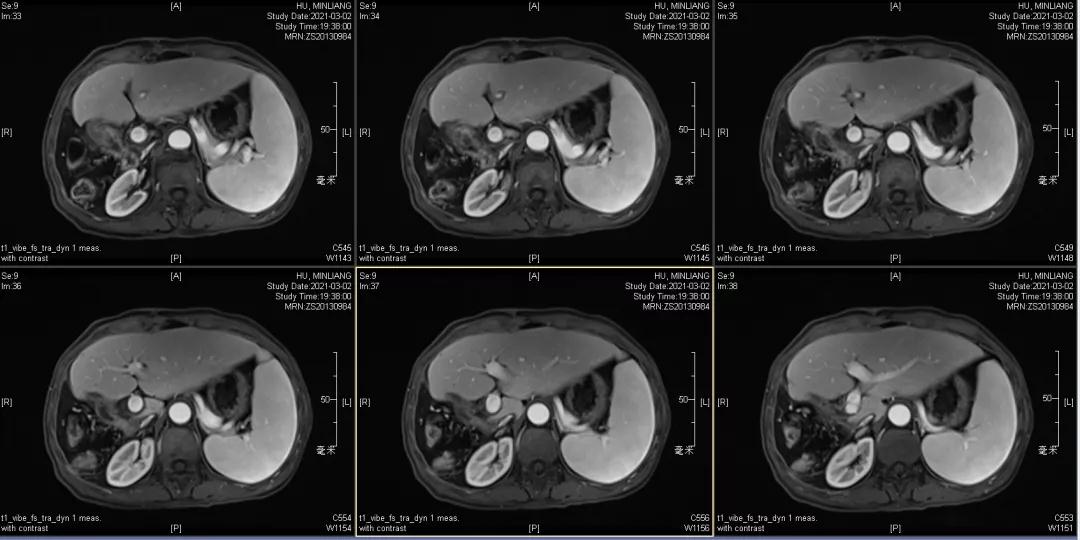

肿瘤学评估(用药后2个月对比6个月):肝内主瘤明显缩小,动脉期强化降低;子灶消失;门脉右支癌栓明显缩小坏死;肺转移灶缩小,大部分消失。

Δ治疗过程中病灶影像学变化

用药6个月后:肝脏病灶明显缩小,子灶消失,仅有少量动脉期强化;肺转移单个持续缩小稳定,PET CT活性弱;HBV DNA 转阴;可考虑转化切除。

术后1月复查:磁共振肝内未见肿瘤复发,肺部单个肿瘤稳定。

术后末次随访2021年12月6日,肝内未见明显病灶,肺部病灶稳定1.3cm。

Δ末次随访MRI及AFP变化